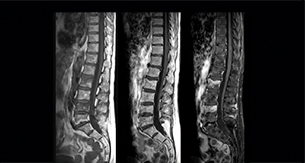

Spine scans must be fast and complete

“In our spine cases, we use mDIXON TSE for patients with degenerative and inflammatory spine issues, vertebral fractures and vertebral and paravertebral tumor characterization,” says Dr. Lefebvre. “It provides, in a single acquisition, different contrasts so we can both visualize and characterize spinal, focal or diffuse spine lesions.”

“mDIXON TSE makes real a difference in cases of acute and traumatic spinal injuries, where it allows us to reduce the scan time by only using a limited number of sequences. For patients in pain, who come from the emergency unit and need surgery, for example, MRI must be very fast. With a single T2-weighted acquisition we can assess spinal cord, vertebral disc and ligament wholeness with in-phase images, as well as trabecular fracture and edematous changes with water images.”

Dr. Lefebvre cites other frequent examples of spinal diseases that benefit from the mDIXON technique. “In cases of vertebral disc herniation or degenerative discs, for example, we don’t have to choose between fat or no fat images. We can assess morphological changes in the endplate with in-phase images from T2-weighted sequences and in the water image from the same acquisition we will see inflammatory changes into endplates.”